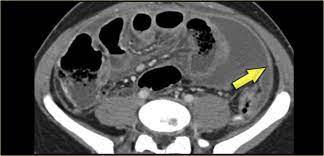

Elevation of osteopontin in mesothelioma cells is limited to exposure to short but not long single wall carbon nanotubes. assistant professor of radiology — view full profile paul j. Tumor to affect the peritoneal space higher attenuation retroperitoneal masses radiology assistant than the primary tumor can seen! Sclerosing mesenteritis can be categorized into three subgroups on the basis of the predominant tissue type in the mass. A cancer diagnosis may be overwhelming. Nurses in the diagnostic radiology department provide education and support to the patient and family before, during and after the procedure. Making a selection of a reliable mesothelioma lawyer is important, however it is not an easy task; assistant professor of oncology, chief of endoscopy, division of gastroenterology, department of medicine. This is why life expectancy often depends on whether a person is treated at a specialized cancer center where they have access to the best mesothelioma doctors. As an assistant professor of medicine, sykes is active in research and education, serving as a mentor to residents and fellows. There's no history of syncope or. We just do it from the pictures. Asbestos cancer news mesothelioma lawsuit.

Foster, mihir patel, betty l. Common findings small nodules in a perilymphatic distributi. Ct, cystic mesothelioma, mesothelioma, oncologic imaging,. Pleural effusions are common and may obscure the presence of the underlying pleural thickening. The most common mesothelioma finding on radiographs is unilateral, concentric, plaque like, or nodular pleural thickening. The radiology assistant lung hrct basic interpretation. Professor of radiology and medicine. mesothelioma lawyers specialise in taking on the cases of people who have been diagnosed with this condition and putting together a structured case for compensation.